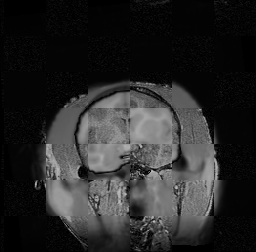

For each of the 10 subjects, we show checkerboard slices in each direction (1) before registration, first row; (2) after rigid->scaleversor->affine registration, second row; and (3) after BSpline registration, third row.

Issac

Issac is a good example of BSpline registration failure.

Ron noted, the reason might be that Issac had his mouth open, unlike most of the subjects registered successfully.